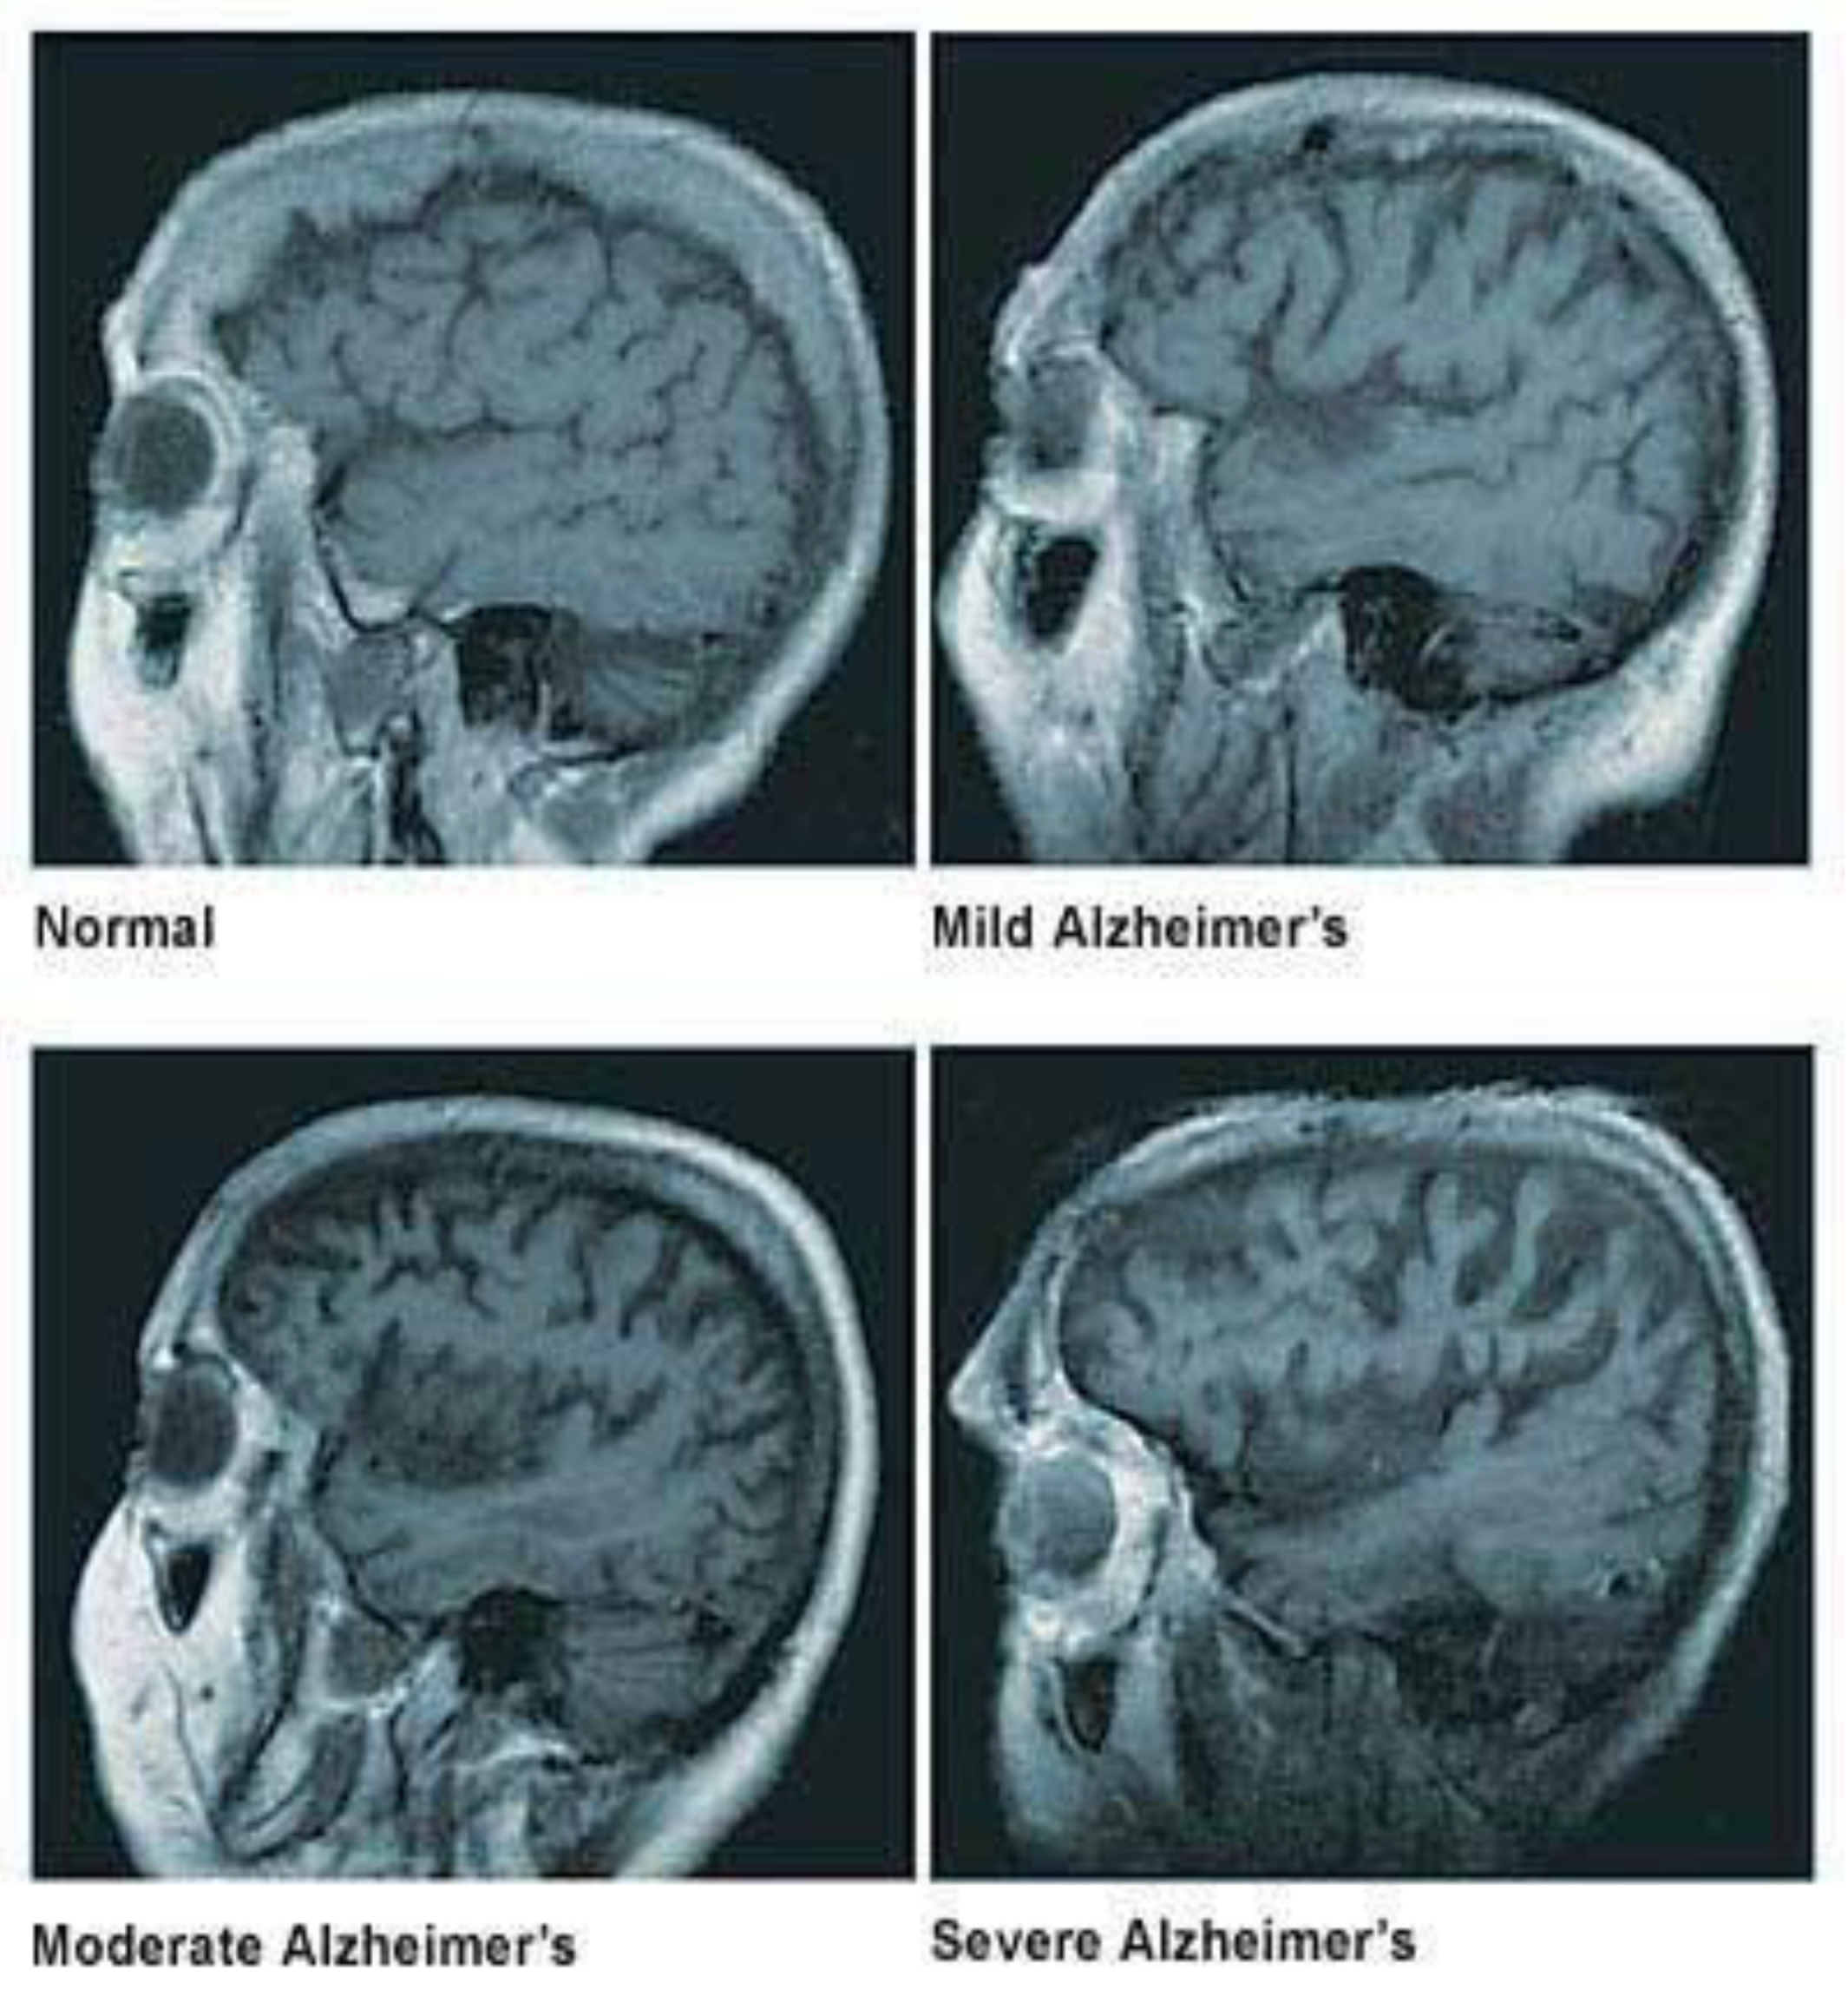

1.1. Loss of Neuronal Connections & Cell Death in AD

- Pini, L.; Pievani, M.; Bocchetta, M.; Altomare, D.; Bosco, P.; Cavedo, E.; Galluzzi, S.; Marizzoni, M.; Frisoni, G.B. Brain atrophy in Alzheimer’s Disease and aging. Ageing Res. Rev. 2016, 30, 25–48. [Google Scholar] [CrossRef] [PubMed]